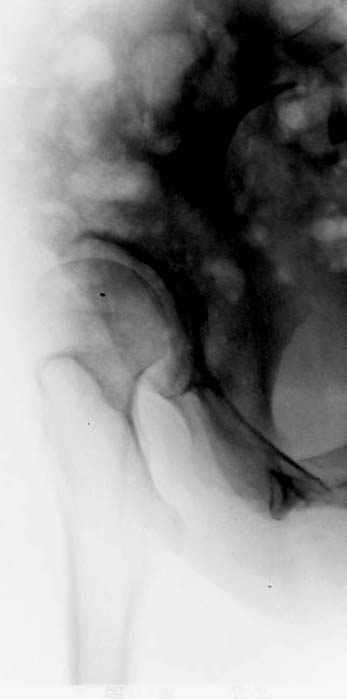

послеоперационные, с учетом биомеханики

сустава #11

отдаленный результат #12

№ 11-12 послеоперационные, с учетом биомеханики

сустава